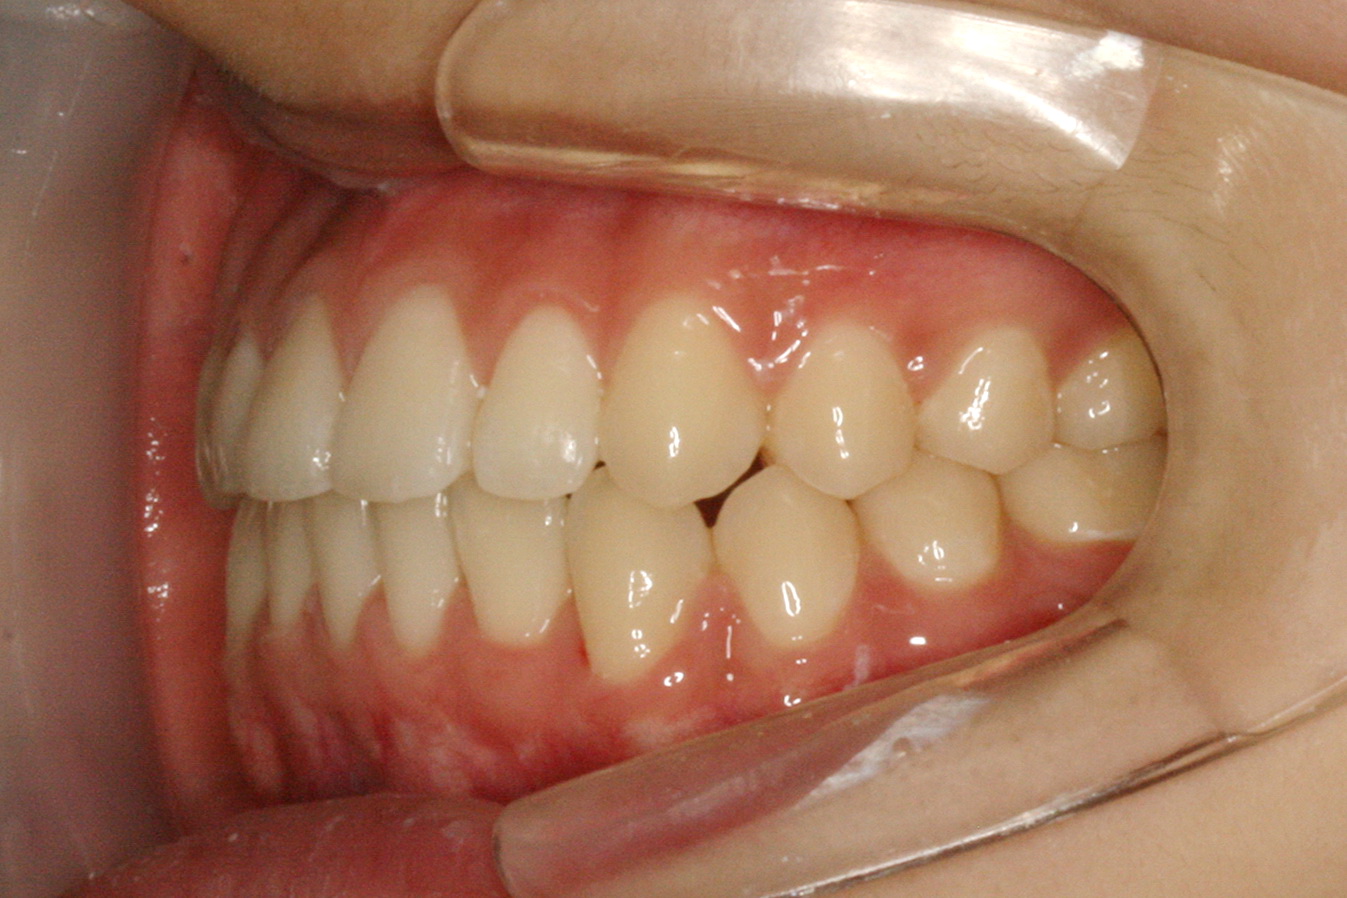

맹출유도교정

보철교정